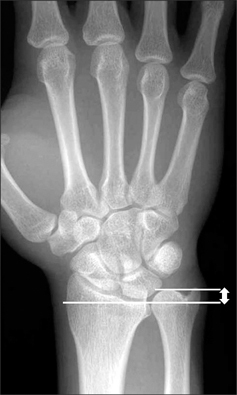

What conditions are associated with the pathological finding of this XR? What would you expect to find on physical exam?

Ulnar Positive Variance

What conditions are associated with the pathological finding of this XR?

Ulnar Negative Variance

How does position of the forearm affect ulnar variance?

A pronated grip view is the best to determine your ulnar varience

How is the load distribution in the wrist affected by ulnar variance?